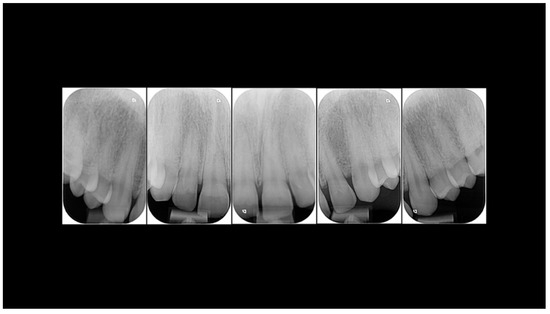

Case Report